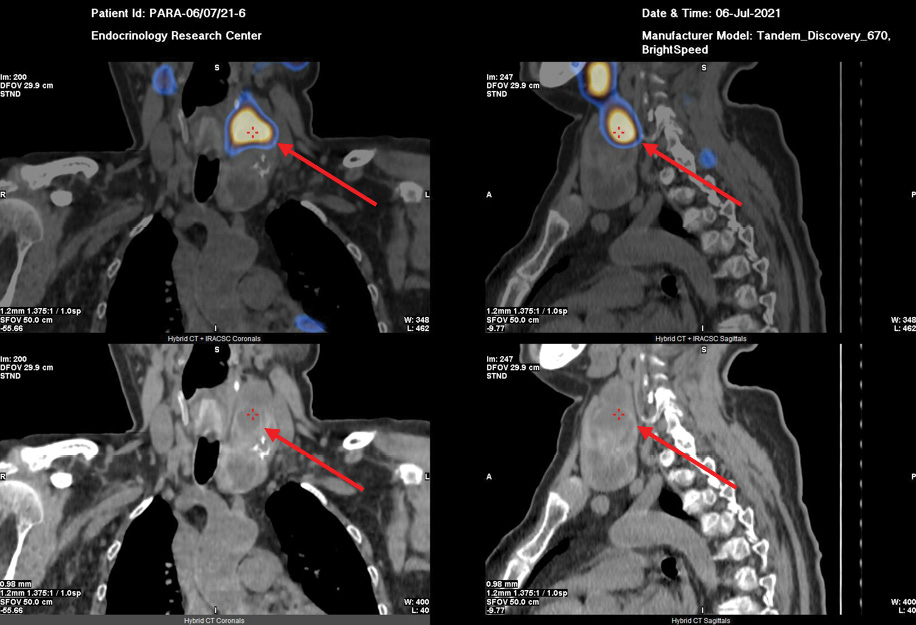

В ходе обследования в ФГБУ «НМИЦ эндокринологии» Минздрава России подтвержден ПГПТ: на фоне гиперкальциемии (Са скорр. на альбумин 2.71 ммоль/л) зафиксировано повышение сывороточной концентрации ПТГ до 1915 пг/мл (15–65), на фоне регулярного приема цинакальцета 60 мг в сутки и длительно некомпенсированного дефицита витамина D (11.8 нг/мл) (табл. 2), а также гипомагниемии (0,64 ммоль/л). Кальциурия не оценивалась ввиду значительного снижения СКФ (до 28 мл/мин/1,73 м²). Проведена топическая диагностика: при УЗИ (рисунок 1) не визуализировано объемное образование околощитовидной железы из-за большого объема конгломерата узлов в левой доле щитовидной железы (European Thyroid Imaging Reporting and Data System — EU-TIRADS 3). Проведена планарная сцинтиграфия с ОФЭКТ/КТ с Tc-99m — Технетрила (MIBI) (рисунок 2), в ходе которой и была определена необычная локализация образования: «левая доля ЩЖ была представлена конгломератным узловым образованием неоднородной структуры, к задней поверхности средней трети левой доли щитовидной железы прилежит образование с четкими ровными контурами овоидной формы гомогенной структуры, размерами 32х37х82 мм, в верхней трети данного образования отмечается гипераккумуляция радиофармпрепарата (РФП); в местах типичного расположения паращитовидных желез дополнительных образований, накапливающих РФП, не определялось. В других областях шеи и верхнего средостения патологического очагового накопления РФП не выявлено.

Риcунок 2. Планарная сцинтиграфия с ОФЭКТ/КТ с Tc-99m — Технетрила (MIBI).